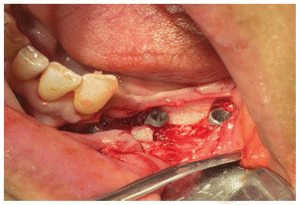

Due to the size of the lesion a mandibular titanium rod was placed to preserve the the lower portion of the mandible and part of the ascending ramus and condyle of the mandible (Figures 6,7,8) In the panoramic rx, the placement of the titanium rod can be seen to fix the ascending ramus with the condyle and the right side of the mandible with the resection to the level of the left lower canine (Figure 9).

Subsequently, a Walter Lorenz Titanium mesh (Figure 10,11) was used to contain the autologous bone that was obtained from the anterior iliac crest mixed with BMP2 morphogenetic protein (Cowell PLUS BMP), as well as Alogen bone mixed with growth factors and membranes with the Chuckron technique (Figure 12, 13,14)